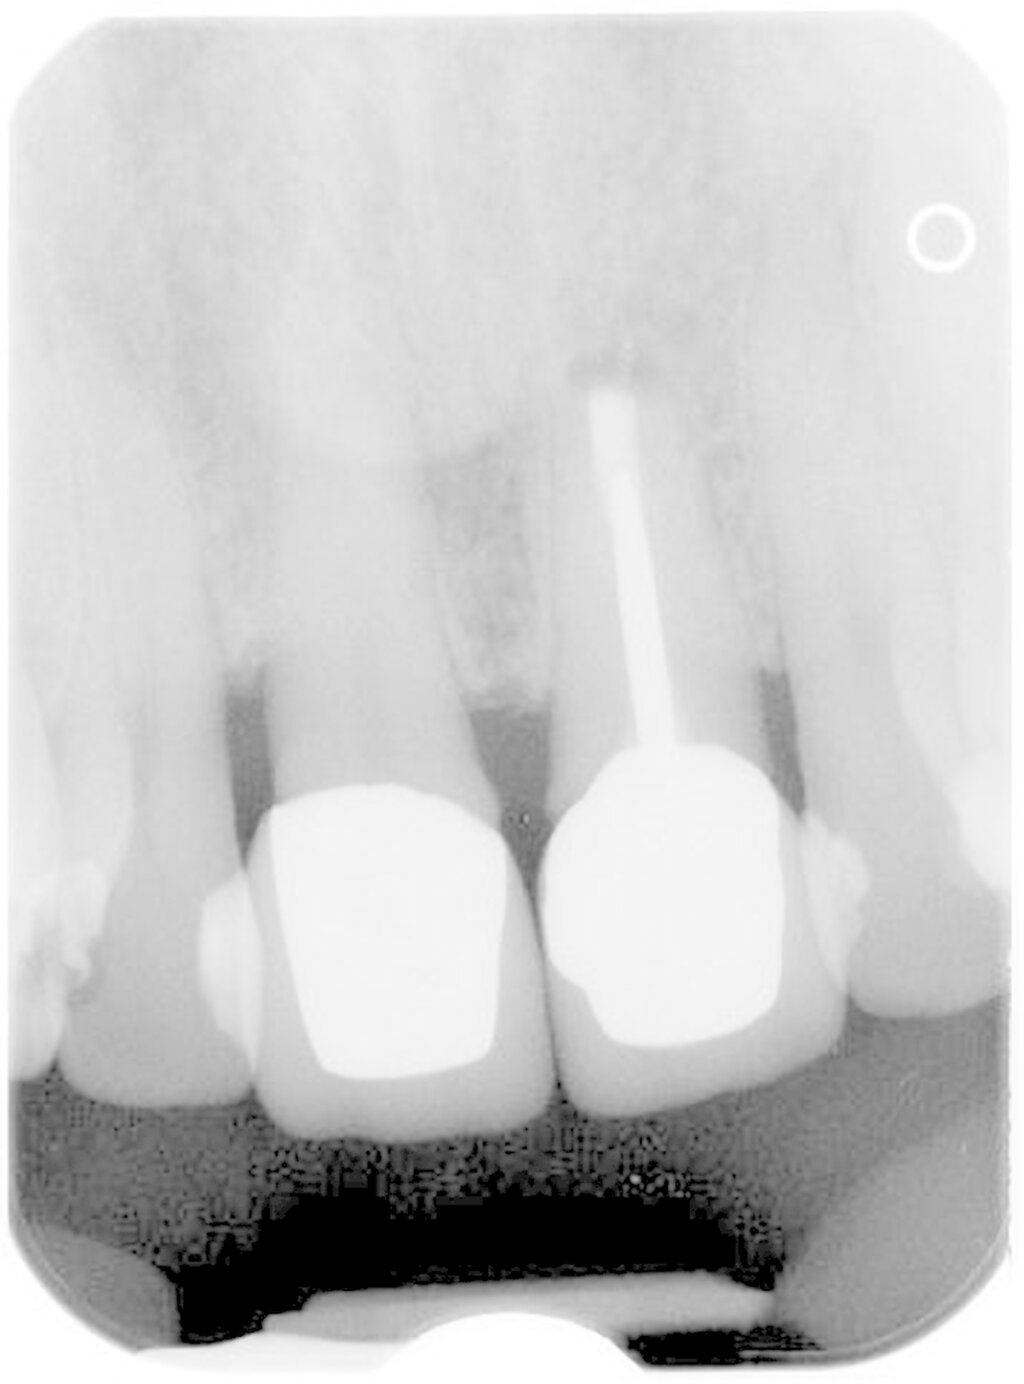

Bezüglich der Zahnlokalisation zeigen eigene Zehn-Jahres-Daten signifikante Unterschiede zugunsten des Oberkiefers. Bei der differenzierteren Betrachtung von Frontzähnen, Prämolaren und Molaren zeigte der paarweise Vergleich signifikante Unterschiede zwischen den Molaren und den Frontzähnen sowie den Molaren und den Prämolaren. Die Unterschiede zwischen Frontzähnen und Prämolaren waren nicht signifikant [Kreisler et al., 2018]. Bei diesem Phänomen handelt es sich möglicherweise mitunter um ein statistisches Problem. Betrachtet man nämlich jede einzelne Wurzel als Lokus des potenziellen Scheiterns, steigt natürlich das Gesamtrisiko bei einem mehrwurzeligen Zahn. Das Vorhandensein von Isthmen als Ursache wurde in der Literatur diskutiert [Kim et al., 2016]. Allerdings stellt das Erkennen von diesen und deren Einbeziehen in die Präparation und Abdichtung heutzutage eigentlich eine Selbstverständlichkeit dar (Abbildung 4). Gleiches gilt für die Berücksichtigung der palatinalen Wurzel bei Oberkiefermolaren.